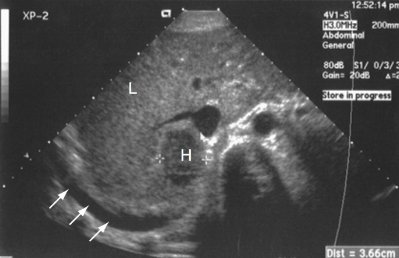

This image displays a

Hypoechoic solid mass